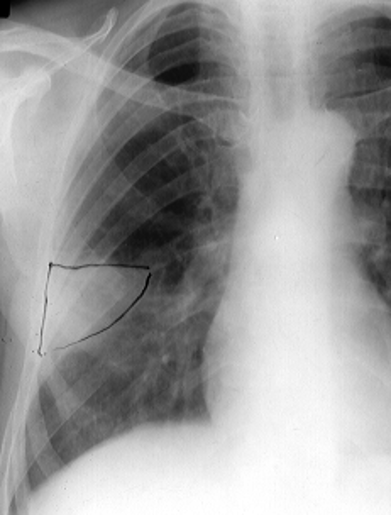

Rx toracică, incidență P-A

DESCRIERE:

DX: emfizem pulmonar

DD: